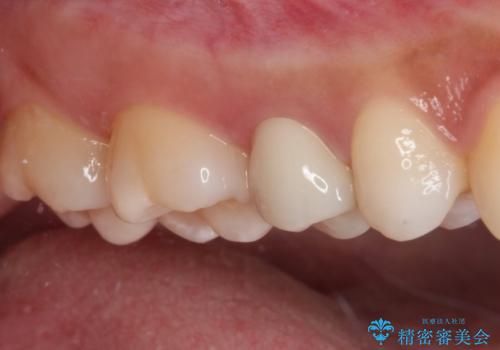

かなり深い位置にまで虫歯が及んでいたため、かなりの量を引っ張り出す必要があり、残された歯根は短く小さい状態となりました。

今後も定期的にレントゲンを撮るなど、経過を追っていく必要があります。